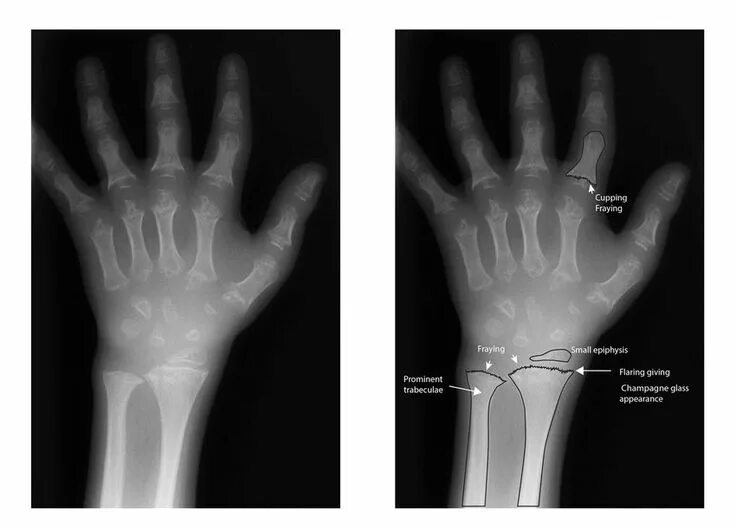

Source x rays